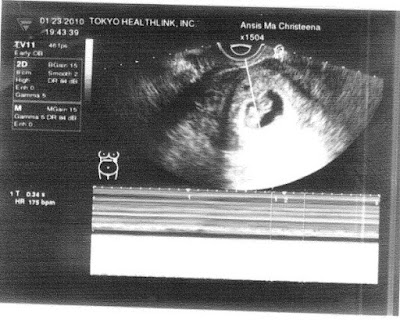

![]() |

| OB Sonologist and Me during 8th week Ultrasound |